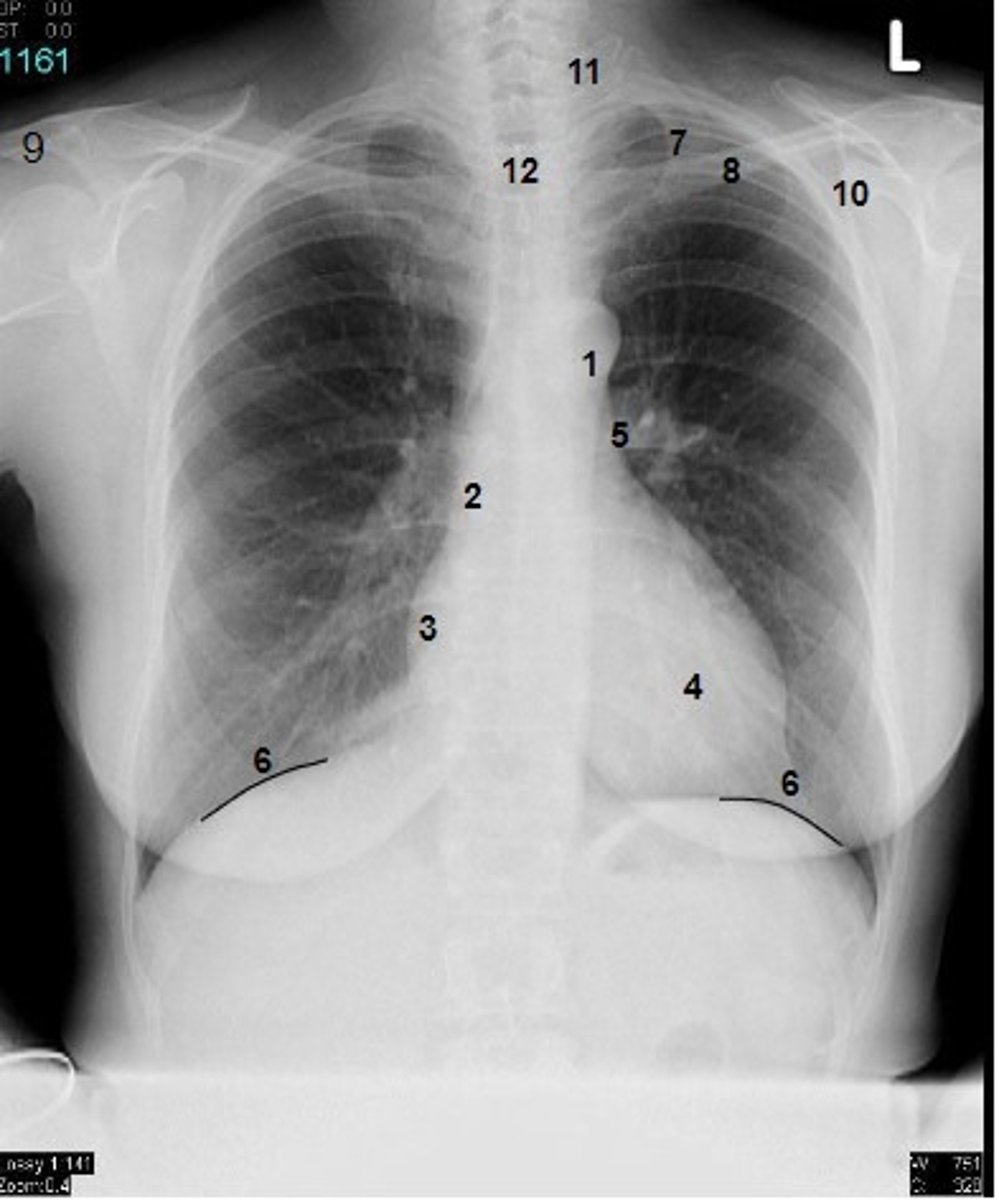

1

at what number is the arch of aorta?

2

at what number is the superior vena cava

3

at what number is the right atrium

4

at what number is the left ventricle

5

at what number is the primary bronchus

6

at what number is the dome of diaphragm

7

at what number is the first rib

8

at what number is the clavicle

9

at what number is the acromion of scapula

10

at what number is the coracoid process of scapula

11

at what number is the transverse process of vertebra

12

at what number is the spinous process of vertebra